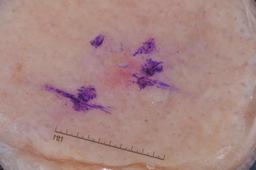

{

"age_approx": 70,

"anatom_site_general": "lower extremity",

"concomitant_biopsy": true,

"dermoscopic_type": "contact non-polarized",

"diagnosis_1": "Indeterminate",

"diagnosis_2": "Indeterminate epidermal proliferations",

"diagnosis_3": "Solar or actinic keratosis",

"diagnosis_confirm_type": "histopathology",

"image_type": "dermoscopic",

"lesion_id": "IL_1264770",

"melanocytic": false,

"sex": "male"

}